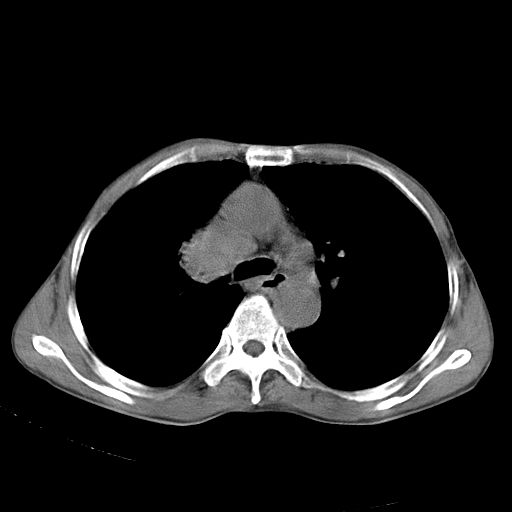

以下是引用苯小孩在2007-5-24 12:47:00的发言:[br]右侧肺门处不均匀密度软组织块影,远端肺组织见斑片模糊影,纵隔内淋巴结明显肿大,边界不清.<纵隔窗第12层面支气管内似见软组织结节>[br]考虑:1、右侧中央性肺癌并阻塞性肺炎并纵隔淋巴结转移可能性大.建议强化或纤支镜进一步检查.[br]2、隆突下淋巴结肿大/食道病变?请做鉴别检查.

以下是引用zhangzhongshou在2007-5-24 12:55:00的发言:[br]1、右肺中叶中心型肺癌并右肺门、隆突下、纵隔淋巴结转移。右肺中叶阻塞性肺炎。

以下是引用jw-830在2007-5-24 15:24:00的发言:[br][br] [br] 考虑右肺中央型肺癌并阻塞性炎症,右肺门及纵隔淋巴结转移。 [br] [br][br]